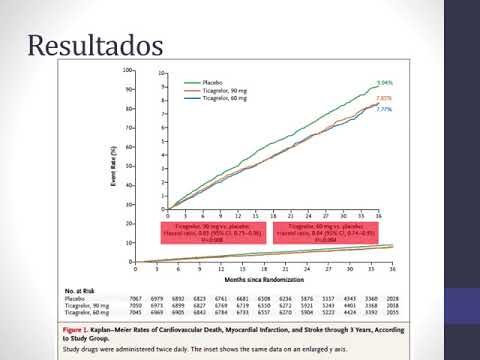

Tratamiento con Ticagrelor en pacientes con IAM. Dra. Florencia Anzivino. Residencia de Cardiología. Hospital C. Argerich. Buenos Aires